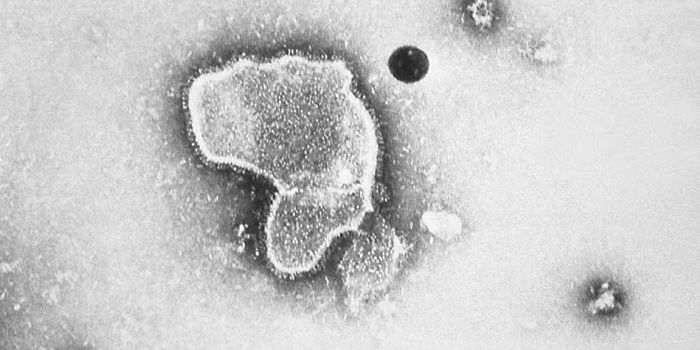

SEP 26, 2022Drug Discovery & DevelopmentIn early April, Pfizer announced a $525 million acquisition of ReViral’s novel therapy for respiratory syncytial v ...